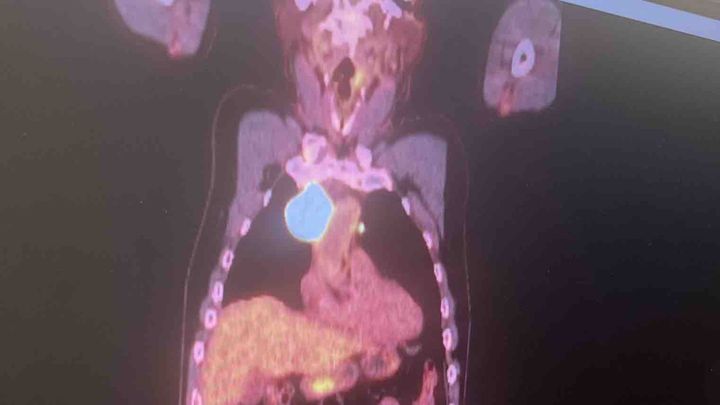

Hola me llamo Noylen J Pino soy la hija de Noel Pino operador de la compañía de Mastec en Miami y he creado este recaudación para mi papá debido a que empieza un tratamiento de quimioterapia por causa de su enfermedad de Linfoma de células B grandes donde ya tiene una masa de más de 5 cm atrás del corazón y ya también alcanzó la garganta.